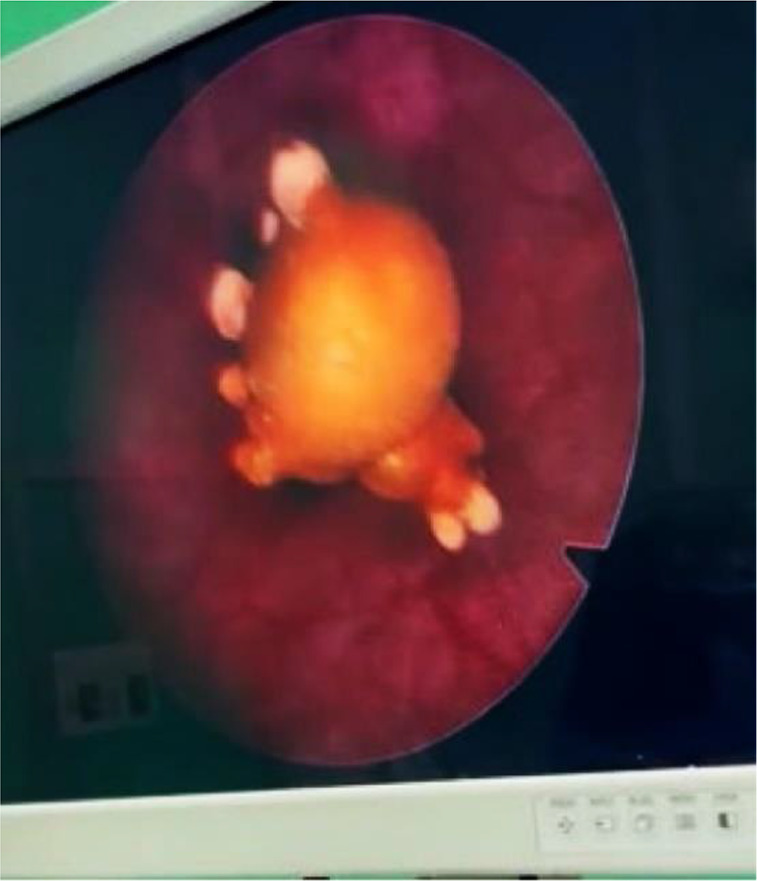

Case presentation: Our case was a 41-year-old woman whose IUD was accidentally discovered in her bladder during a routine ultrasound. The IUD has migrated from its normal position in the uterus to the bladder. The IUD was successfully removed by cystoscopy without any complications.